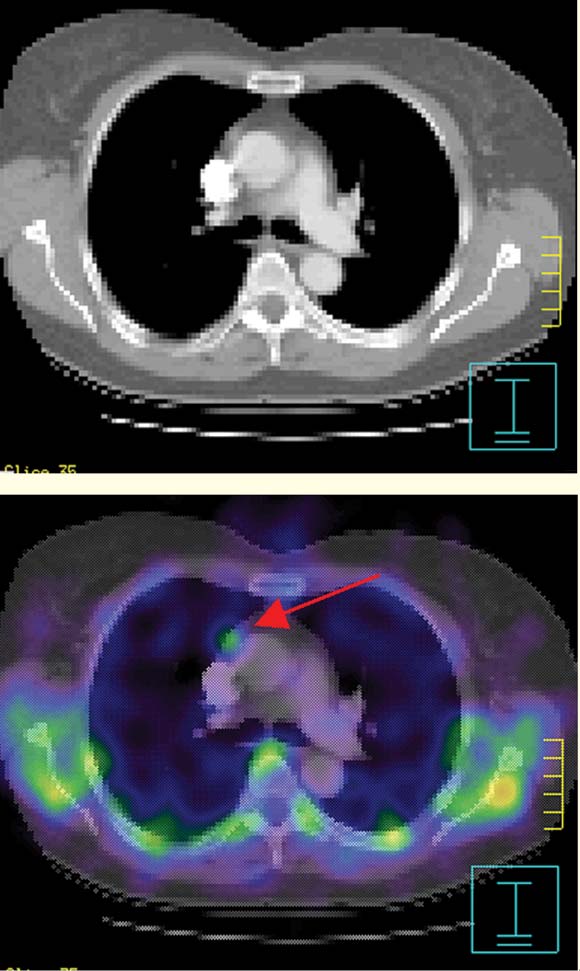

Single-photon-emission computed tomography (SPECT) imaging confirmed the finding in the right mediastinum (Box 2, Figure B). Thoracic computed tomography (CT) showed a 9 mm soft-tissue mass, lying anterior to the aorta at the level of the carina (Box 2, Figure C). Its appearance was non-specific, but incidental lymphoid tissue was considered most likely. Utilising a software co-registration package (Philips/ADAC Laboratories, Milpitas, Calif, USA), the sestamibi SPECT images were fused onto the CT images. The resulting views showed abnormal mediastinal sestamibi activity localised to the soft-tissue mass, suggesting the presence of ectopic parathyroid tissue (Box 3).

In our patient, the use of new image-fusion software allowed the accurate integration of both functional and anatomical data on the one image set. This image fusion clearly confirmed abnormal sestamibi activity arising from the mediastinal mass seen on CT, implying the presence of ectopic parathyroid tissue. A similar case of ectopic adenoma detection using this technique has been described previously.14 However, in that report, the CT findings of a 2.0 × 1.0 cm mediastinal mass were clearly abnormal and strongly suggestive of an adenoma.14 Our case is the first to highlight the incremental diagnostic value of image fusion, as the CT, and indeed intraoperative, findings in isolation were inconclusive. After confirming the presence of ectopic parathyroid tissue, a thoracoscopic approach to surgery was undertaken rather than a conventional approach.